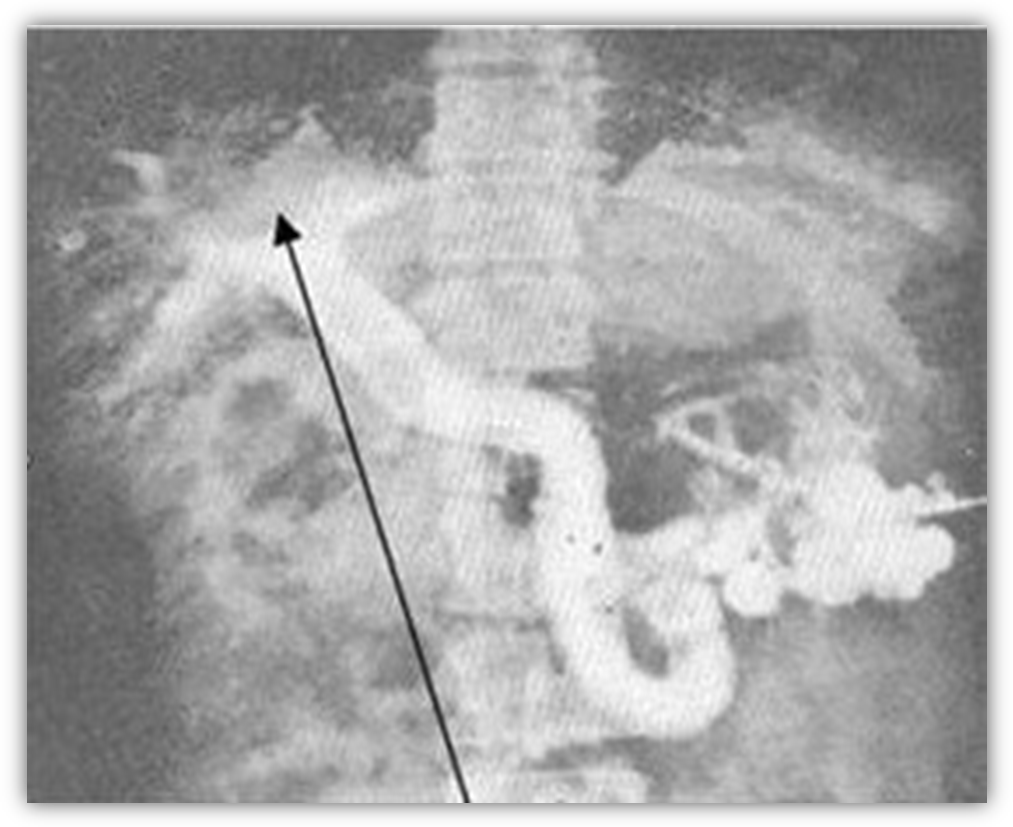

7. Спленопортографія

Наявність підпечінкового блоку (вказано чорною стрілкою)